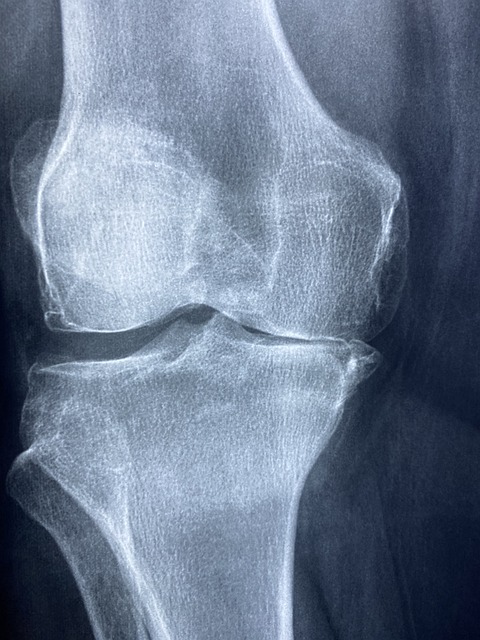

◐ 콜라겐과 관절염 · 연골

관절염은 관절연골이 파괴되고 관절에 염증이 생겨 나타나는 질병입니다. 관절은 두 개 또는 그 이상의 뼈들이 맞닿는 곳인데 관절을 이루는 뼈들의 끝에는 연골이라는 부드러운 재질로 싸여 있어 쿠션과 같은 역할을 해주어 관절이 쉽에 움직일 수 있도록 도와줍니다. 이토록 중요한 연골은 주로 콜라겐과 콘드로이친황산으로 구성되어 있습니다.

외국에서는 콜라겐을 퇴행성 관절염 등의 통증치료에 단기간에 한해 보조로 사용되는 경우가 있지만 장기간의 유효성이 입증되지는 않았다고 합니다.